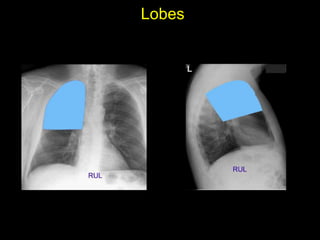

The document discusses the anatomy of the chest x-ray and CT scan by describing the lobes of the lungs and their locations. It also mentions the heart, mediastinum, hilum, and ribs. Several axial, coronal, and sagittal CT images are included with labels pointing out structures like the trachea, bronchi, lobes of the lungs, and fissures. In summary, the document provides an overview of lung and chest anatomy as seen on x-rays and CT scans through text descriptions and labeled medical images.